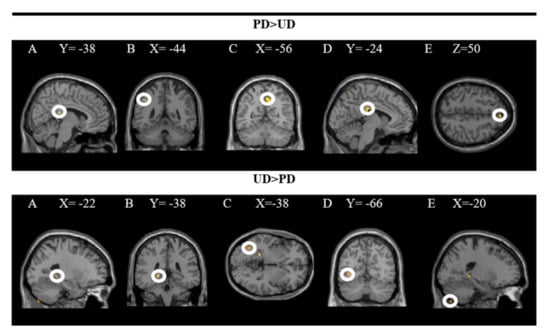

The groups in the rear R cingulate gyrus, L inferior parietal lobe, R pre(cuneus), L middle cingulate gyrus, and R superior frontal gyrus were activated more strongly when comparing the pleasant (PD × RD + PD × ED) and the unpleasant (UD × RD + UD × ED) plates. In contrast, the L hippocampus, L inferior occipital gyrus, and L exterior of the cerebellum were activated more significantly when comparing unpleasant to pleasant dishes. In these analyses, a significance level of p = 0.001 was established without correction. The results are presented in Figure 3 and the coordinates of the peak are in Table 1.

Figure 3.

Brain regions activated more strongly to pleasant vs. unpleasant dishes (PD > UD) and to unpleasant vs. pleasant dishes (UD > PD).

The upper part of the figure shows a T-map with a threshold of p < 0.0001 uncorrected for multiple comparisons (T > 3.2), which is superimposed on the mean anatomical image of all subjects (NIM-space). A: R posterior cingulate gyrus; B: L inferior parietal lobe; C: R precuneus; D: L middle cingulate gyrus; E: R superior frontal gyrus. The lower part shows an uncorrected threshold T map at p < 0.0001 for multiple comparisons (T > 4.5), which is superimposed on the mean anatomical image of all subjects (MNI-space). A and B: L hippocampus; C and D: L inferior occipital gyrus; E: L outer cerebellum. See the corresponding coordinates of the peaks in Table 1.

The findings showed significant activity in the following areas: L putamen, R putamen, R pallidum, R insula and R middle cingulate gyrus while processing dishes with emotional descriptions (ED × PD). The results of the inverse contrast (RD × PD) indicate greater activity in the R superior parietal and ventral DC when the dishes on the restaurant menu with a rational description (vs. emotional) are processed. In these analyses, a significance level of p = 0.005 was established without correction. The results are presented in Figure 4 and the coordinates of the peak are in Table 2.

Figure 4.

Brain regions activated more strongly to emotional vs. rational description (ED > RD) and rational vs. emotional descriptions (RD > ED).

The upper part of the figure shows a T-map with a threshold of p < 0.0001 uncorrected for multiple comparisons (T > 2.73), superimposed on the average anatomical image of all subjects (NIM-space). A: L putamen; B: R putamen; C: R pallidum; D: R insula; E: R middle cingulate gyrus. The lower part shows a T map with a threshold of p < 0.0001 uncorrected for multiple comparisons (T > 3.2), superimposed on the average anatomical image of all subjects (MNI-space). A and B: superior parietal R; C, D and E: ventral DC. See the corresponding coordinates of the peaks in Table 2.